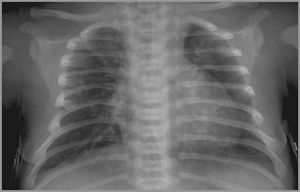

Newborn 32 week gestation need ventilation since birth What is your Dx?

Congenital heart dis...VSD or TOG

Transposition of the great artheries?

The R) lung not developed.